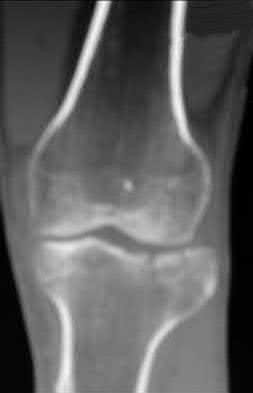

This patient presents with a Schatzker IV tibia plateau fracture with lower extremity neurologic deficits. The next best step would be to investigate for an acute vascular injury with ankle-brachial index measurements.

Fracture-dislocations of the knee must be suspected with all Schatzker type IV injuries as this fracture pattern is usually associated with high energy trauma. Identifying this injury should prompt a thorough assessment of the neurovascular structures across the knee. After closed reduction and emergent immobilization of the knee, ankle brachial indices (ABI) must be immediately performed. If